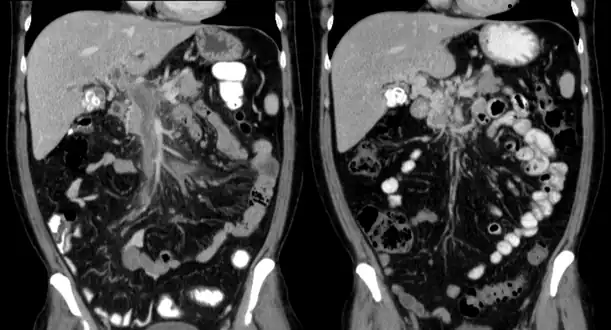

Portal vein thrombosis seen with computed tomography.

The diagnosis of portal vein thrombosis is usually made with imaging confirming a clot in the portal vein; ultrasound is the least invasive method and the addition of Doppler technique shows a filling defect in blood flow. PVT may be classified as either occlusive or nonocclusive based on evidence of blood flow around the clot.[5] An alternative characterization based on site can be made: Type 1 is limited to the main portal vein, Type 2 involves only a portal vein branch (2a, or 2b if both branches are affected), and Type 3 if clot is found throughout both areas.[8] Determination of condition severity may be derived via computed tomography (CT) with contrast, magnetic resonance imaging (MRI), or MR angiography (MRA). Those with chronic PVT may undergo upper endoscopy (esophagogastroduodenoscopy, EGD) to evaluate the presence of concurrent dilated veins (varices) in the stomach or esophagus.[3] Other than perhaps slightly elevated transaminases, laboratory tests to evaluate liver function are typically normal.[1] D-dimer levels in the blood may be elevated as a result of fibrin breakdown.